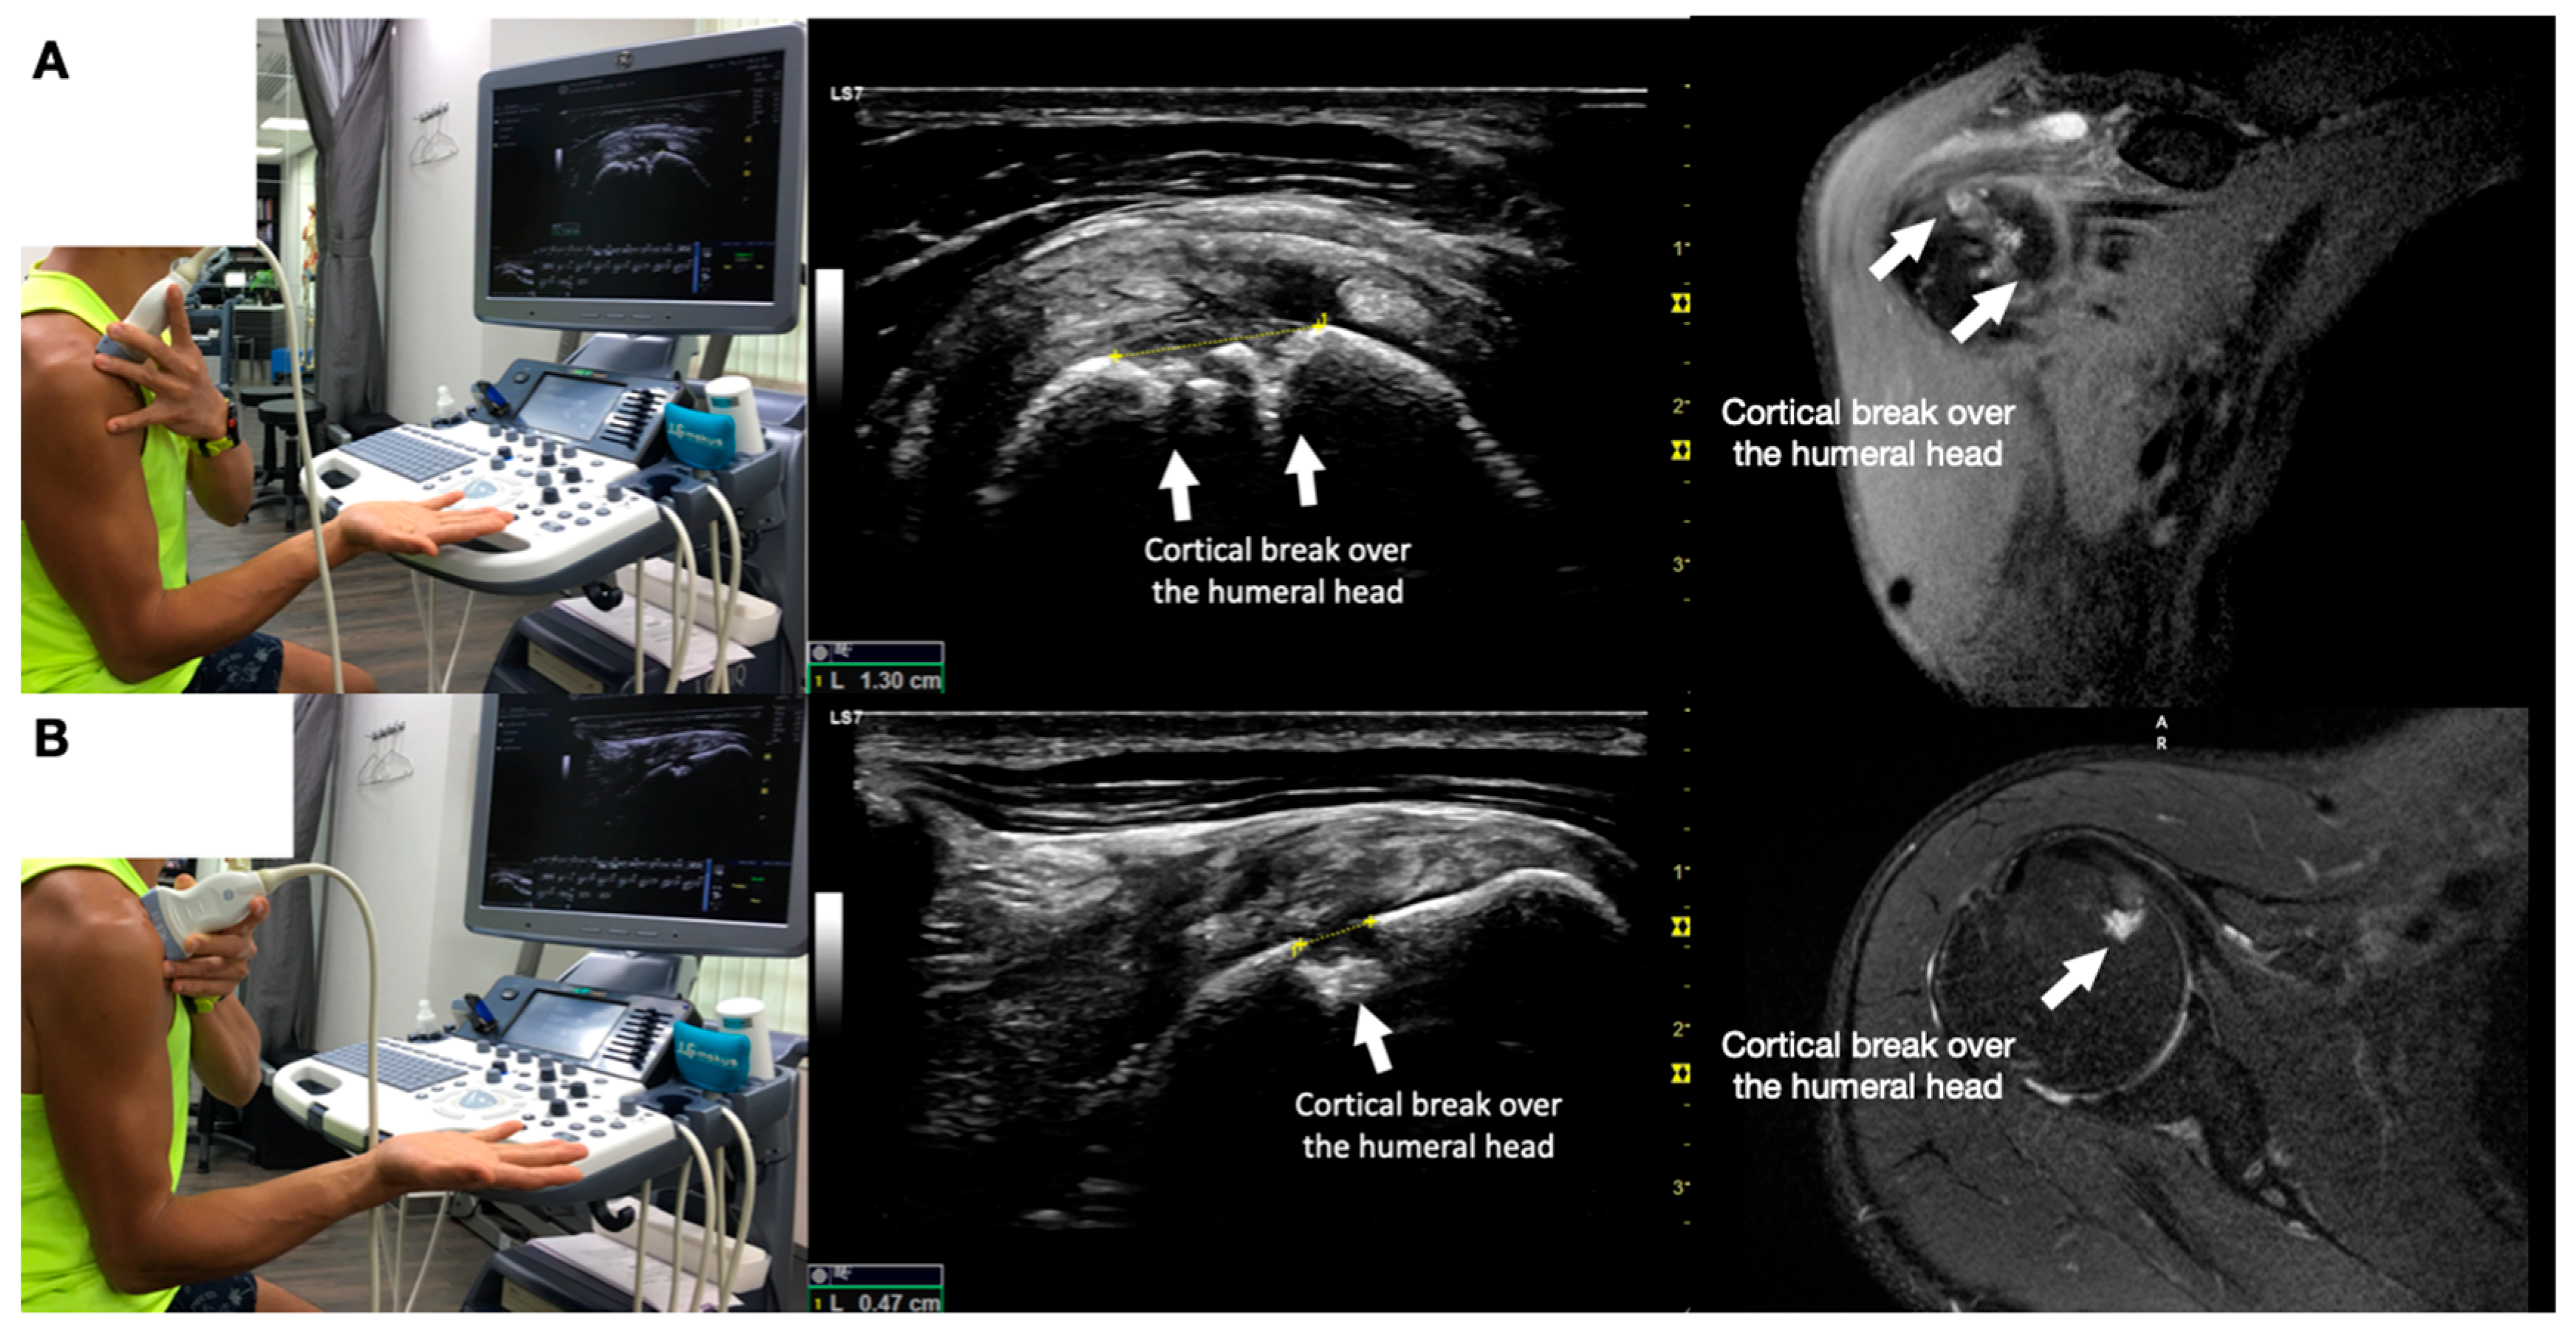

Shows the sonographic appearance of a cortical break over the humeral head deep in the subscapularis tendon and its corresponding magnetic resonance image appearance. The white arrows pointed to the cortical break over the humeral head. (A) Shows the view of the break in its long axis. (B) Shows the short axis of the cortical break. This report aimed to present a case of painful anterior shoulder snapping, apparently due to the compression of thickened fibrotic bursa between the subscapularis and the short head of the bicep during external and internal rotation of the humerus. However, an ultrasound-guided injection of the thickened and fibrotic bursa did not reproduce the pain or improve snapping. Ultrasound scanning identified a cortical break of the humeral head underneath the subscapularis as a potential mechanical effect of snapping. Nevertheless, an ultrasound-guided injection of the cortical break reproduced and temporarily reduced the pain with snapping and residual anterior shoulder pain, but it did not alter the snapping or weakness in the right shoulder flexion with the humerus in external rotation. A 46-year-old musculoskeletal physician with a 10-month history of on-and-off anterolateral right shoulder pain and snapping [1,2] presented a numerical rating scale (NRS) score of 6–8/10. He had noticed the anterior right shoulder nonpainful snapping for several years and with recent aggravation. Substantial dysfunction and impairment were evidenced by 80% pain and 70% disability sub-scores on the Shoulder Pain and Disability Index (SPADI) [3], with a total score of 73.8% out of a maximum severity of 100. His pain and dysfunction were unresponsive to all manner of conservative musculoskeletal treatments, which substantially affected his sleep and vocation as a musculoskeletal physician. Snapping was prominent during internal and external rotation of the glenohumeral joint at different degrees of abduction and/or flexion. Physical examination revealed a normal range of motion of the shoulder. Tenderness was observed over the anterolateral part of the shoulder over the lesser tuberosity. Internal and external rotation of the shoulder revealed snapping over his anterolateral shoulder, and the most severe snapping occurred when he flexed and abducted his shoulder to 90°, followed by internal and external rotations. Resisted shoulder flexion power tested by the treating physician with the elbow straight and the shoulder flexed at 90° with the internally rotated humerus (thumb down, similar to the empty can sign), both straight and abducted shoulder, had normal power and no pain. However, the power of resisted shoulder flexion with the elbow straight and the shoulder flexed to 90° with the humerus externally rotated (palm up) was diminished and associated with pain (Video S1). Dynamic ultrasound scanning of the painful anterior shoulder snapping during internal and external rotation was shown in Video S2. The cortical break underneath the subscapularis, suspected due to the mechanical effects of the snapping and causing the anterior shoulder pain, was demonstrated in Figure 1. Ultrasound-guided digital palpation of the cortical break reproduced the patient’s usual pain in the anterolateral shoulder.